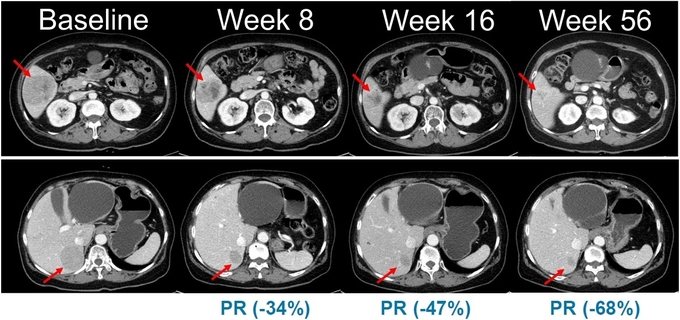

이 같은 기전적 차별성을 바탕으로 벨바라페닙과 코비메티닙 병용요법은 기존 BRAF 단일체·MEK 억제제 병용 치료의 한계를 보완하고, 보다 폭넓은 유전자 변이 환자군에서 임상적 이점을 제공할 수 있는 전략으로 평가받고 있다. 실제로 2021년 미국임상종양학회(ASCO)에서 발표된 연구에서는 NRAS 돌연변이 흑색종 환자 대상 병용요법에서 종양 병변 감소가 관찰된 바 있다.